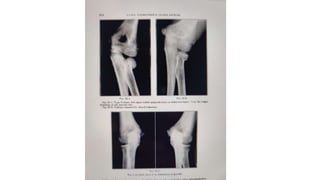

• Common type of injury at upper radial epiphysis is type 2

• Produced by valgus force on the elbow , resulting in angulation of

radial head

• Reduction can be achieved by holding the extended elbow in varus

and directly pressing over the radial head

• If angulation is > 15° after closed reduction , supination – pronation

may get affected and open reduction is indicated

• Radial head should not be excised in children , if done loss of radius

growth wll produce progressive radial deviation at the wrist joint and

valgus deformity at the elbow

• Common typeof injury at upper radial epiphysis is type 2 • Produced by valgus force on the elbow , resulting in angulation of radial head • Reduction can be achieved by holding the extended elbow in varus and directly pressing over the radial head • If angulation is > 15° after closed reduction , supination – pronation may get affected and open reduction is indicated • Radial head should not be excised in children , if done loss of radius growth wll produce progressive radial deviation at the wrist joint and valgus deformity at the elbow